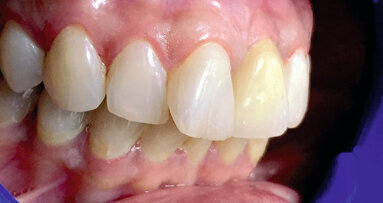

Cas 2c : prothèses en bouche